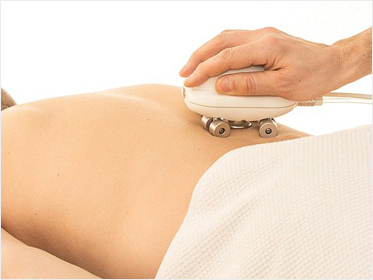

PainEraser

������ �̿��ϰ� ������ �����ϴ� ���� ȿ�����Դϴ�.

PainEraser

���Ǽ� ���� ��ȭ ���� �ڱ� ��ġ

��ġ�� ������������ ���ο� �ϴ� ȯ�ڵ��� ������� �ǽ��մϴ�.

��ġ�� ������������ ���ο� �ϴ� ȯ�ڵ��� ������� �ǽ��մϴ�.

PainEraserġ�� ���

������ �¿�ġ��, �鿪 �� ��ġ��, PainView, PainEraser

PainEraserġ�� ����

��ħ���� ������ ġ���̸� ���ۿ��� �����ϴ�. ����/������ ���� �������� ������, ġ��ð��� 10~15�� ������ ª��, �� ġ�� �� ��ٷ� �ϻ��Ȱ�� �����ϸ� ���� ġ�� ȿ���� �����ϴ�.